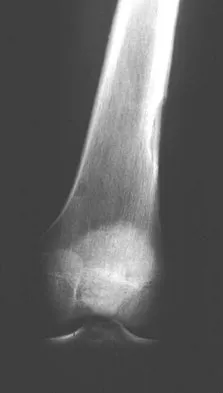

A 10-year-old boy with a history of retinoblastoma now reports right knee pain. AP and lateral radiographs are shown in Figures 3a and 3b. What is the most likely diagnosis?

Explanation

The radiographs show a bone-producing lesion in the femoral diaphysis. The radiographic appearance of small round cell tumors is more permeative with an elevated periosteum and no matrix production. The appearance of this lesion is most consistent with osteosarcoma. Patients who carry the Rb gene are predisposed to osteosarcoma. However, Ewing's sarcoma, primitive neuroectodermal tumor, and osteomyelitis can all occur in this location. Unni KK: Dahlin's Bone Tumors: General Aspects and Data on 11,087 Cases, ed 5. Philadelphia, PA, Lippincott-Raven, 1996, pp 143-160.